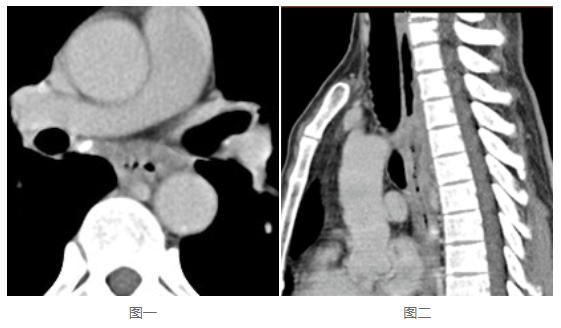

幾乎所有PACS軟件都具備縮放、平移、調窗、測量、電影功能,這部分功能適用于平片、DSA等;也具備分窗、MPR、MIP、VR功能,適用于CT、MR。因此PACS工作站適用于絕大部分影像的后處理,是閱片寫報告的基本要求。那么,這些功能在移動端,采用B/S方式使用時,是不是仍然具備?是不是還適用于絕大部分類型的影像?如果是,那么可以認為具備閱片寫報告的功能要求;如果不是,顯然,對于部分類型的影像,閱片寫報告則相對困難,甚至可能無法判斷。看下這兩張圖:

undefined

這是同一病灶的(de)不(bu)同視角(jiao),圖一是橫斷位,圖二(er)是矢狀位。很明顯(xian),圖二(er)對于食管的(de)侵(qin)蝕顯(xian)示得更為直觀。這應該就是《浙江省數字影像服務專家共識》明確要求“保存檢查時生成的各種成像體位的完整序列影像”的原因。那么(me),如果(guo)PACS在存儲影(ying)像時僅(jin)僅(jin)存儲了橫(heng)斷位,就一(yi)定需(xu)要影(ying)像軟件(jian)本身(shen)能將矢狀(zhuang)位影(ying)像重建出(chu)來。